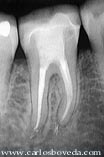

La paciente, de 25 años de edad, fue referida a nuestra consulta para evaluar endodónticamente la zona inferior derecha:

(Haga click en las imágenes para agrandar)

El caso se presentó como un síndorme de diente fisurado en el primer molar inferior derecho (Endodoncia Interactiva, caso # 15, Primera Parte), que fue tratado endodónticamente.

Imágenes clínicas y radiográfico de la condición que presentó el caso y el procedimiento endodóntico realizado (Endodoncia Interactiva, caso # 15, Primera Parte).

Imágenes radiográficas de control a los 6 meses con la restauración.